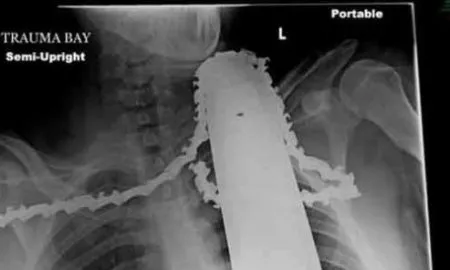

Go Tree Quotes Advises Homeowners On How To Avoid Tree Trimming Injuries With over 36,000 chainsaw related injuries each year by thrifty...